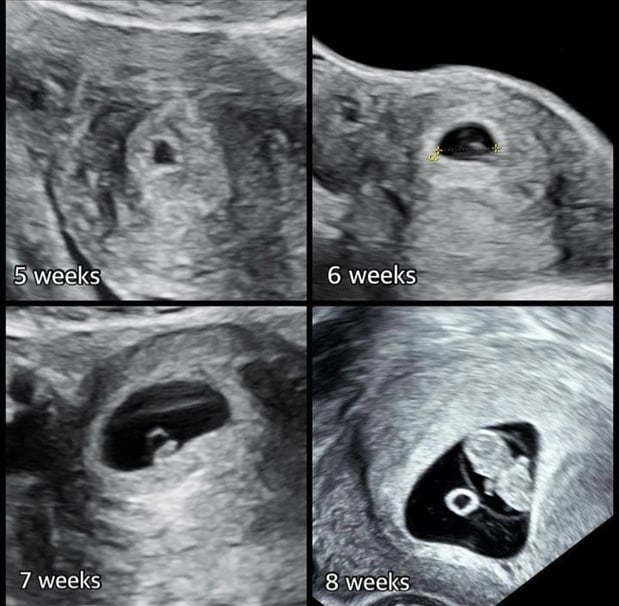

Tasha Crump, is registered by the American Registry of Diagnostic Medical Sonographers (ARDMS) and have over 18 years experience in medical diagnostic sonography specializing in Maternal Fetal Medicine. She is a highly proficient in the art of 3D 4D ultrasound. Tasha has practiced and trained in NYC's top ranked hospitals including Columbia Presbyterian. At Love at First Sight Imaging Studio you'll be in a very comfortable and calming atmosphere for you and your family to bond with your baby. We have state of the art equipment with HD Live to image unbelievably realistic views of your baby. You will fall in Love at First Sight.